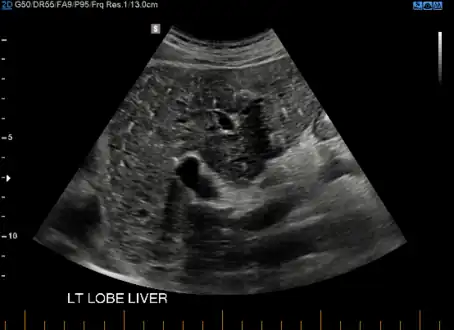

von Meyenburg Complex in ultrasound. Numerous little cysts with ringdown artefacts.

At CT scans, bile duct hamartomas appear as small, well-defined hypo- or isoattenuating masses with little or no enhancement after contrast administration.[3] At MRI, they appear hypointense on T1-weighted images, iso- or slightly hyperintense on T2-weighted images, and hypointense after administration of gadolinium based contrast-agent.[3]